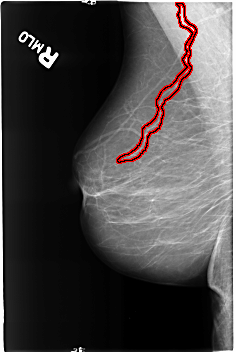

FILE: B_3190_1.RIGHT_MLO.OVERLAY

TOTAL_ABNORMALITIES 1

ABNORMALITY 1

LESION_TYPE CALCIFICATION TYPE VASCULAR DISTRIBUTION N/A

ASSESSMENT 2

SUBTLETY 4

PATHOLOGY BENIGN_WITHOUT_CALLBACK

TOTAL_OUTLINES 1

BOUNDARY